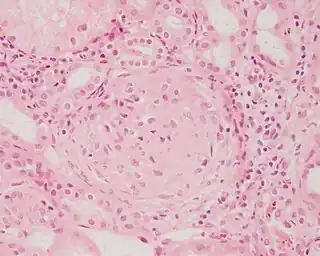

![]() Imagen histopatológica de una muestra de glomerulonefritis con semilunas obtenida de un paciente con glomerulonefritis rápidamente progresiva positiva para anticuerpos anti-MPO-ANCA. Tinción con hematoxilina y eosina. | ||

La glomerulonefritis rápidamente progresiva o extracapilar es un síndrome renal que si no se trata progresa con rapidez a una insuficiencia renal aguda y a la muerte del paciente en cuestión de meses. En el cincuenta por ciento de los casos esta glomerulonefritis se asocia con otra enfermedad de base, como por ejemplo el síndrome de Goodpasture, el lupus eritematoso sistémico o la granulomatosis de Wegener. Los casos restantes son idiopáticos, es decir, se ignora la causa de la aparición de la enfermedad. De todos modos, independientemente de la etiología principal, la glomerulonefritis rápidamente progresiva implica una serie de lesiones del glomérulo del riñón y la presencia de las típicas cicatrices con forma de semiluna en más del cincuenta por ciento de las unidades glomerulares.[1] En ocasiones, debido a esta característica histológica, la enfermedad recibe el nombre de glomerulonefritis semilunar.[1]

Pese a la gran variedad de enfermedades que causan glomerulonefritis rápidamente progresiva, todos los tipos se caracterizan por daño glomerular y formación de semilunas. El daño más grave y la ruptura de la membrana basal glomerular conducen a la pérdida de proteínas plasmáticas. De estas proteínas, se piensa que la fibrina es la que más contribuye a la formación de semilunas. Las células epiteliales que delimitan la cápsula de Bowman responden al estímulo proliferante de la fibrina. También puede haber infiltración de leucocitos como los monocitos y los macrófagos, los que también pueden proliferar bajo la influencia de la fibrina. Estas células proliferantes rodean al glomérulo y lo comprimen por lo que aparece la cicatriz con forma de semiluna que es visible con el microscopio en el material obtenido de una biopsia renal.[2]

Aunque algo arbitrario, actualmente se considera que debe de haber al menos cincuenta por ciento de glomérulos con semilunas para llamar a esta enfermedad glomerulonefritis extracapilar (crescentic).[15]

Anatomía patológica

En la biopsia de estos pacientes se halla una importante proliferación de las células epiteliales de la cápsula de Bowman, con formación de semilunas en los glomérulos.[4] La biopsia renal confirma la presencia de una glomerulonefritis con semilunas epiteliales. Entre las características histopatológicas figura la infiltración del espacio urinario por células mononucleares asociada con la proliferación del epitelio parietal de la cápsula de Bowman o la proliferación extracapilar con formación de semilunas que pueden afectar del treinta al cien por ciento de los glomérulos. En estos se ve un engrosamiento de la cápsula de Bowman con formación de semilunas. También puede haber fibrosis parcial y sinequia del penacho glomerular a la cápsula.[4] Las semilunas, que pueden ser segmentarias o circunferenciales, ocupan todo el espacio de Bowman y ahogan el ovillo capilar, según el estado evolutivo pueden clasificarse en celulares, fibrocelulares o fibrosas y representan fases progresivas del mismo proceso.[4] En la glomerulonefritis rápidamente progresiva de tipo I hay positividad lineal sobre todo para IgG pero después también para C3. Dos tercios de las glomerulonefritis semilunares de este tipo corresponden al síndrome de Goodpasture y el otro tercio carece de manifestaciones pulmonares (síndrome de Goodpasture sin compromiso pulmonar). La lesión glomerular es similar en ambos grupos y se produce por un mecanismo inmunitario antimembrana basal glomerular. Como ya se dijo, el factor desencadenante es un defecto de un componente proteico de la cadena α3 del colágeno de tipo IV.[5] En la enfermedad de tipo II hay positividad granular o nodular o de ambas formas, difusa y global, debido a depósitos de complejos inmunes que con el microscopio electrónico se ven como depósitos densos. Este tipo por lo general corresponde a variedades de la glomerulonefritis aguda difusa, de la glomerulonefritis mesangiocapilar y, menos a menudo, de la enfermedad de Berger.[5]